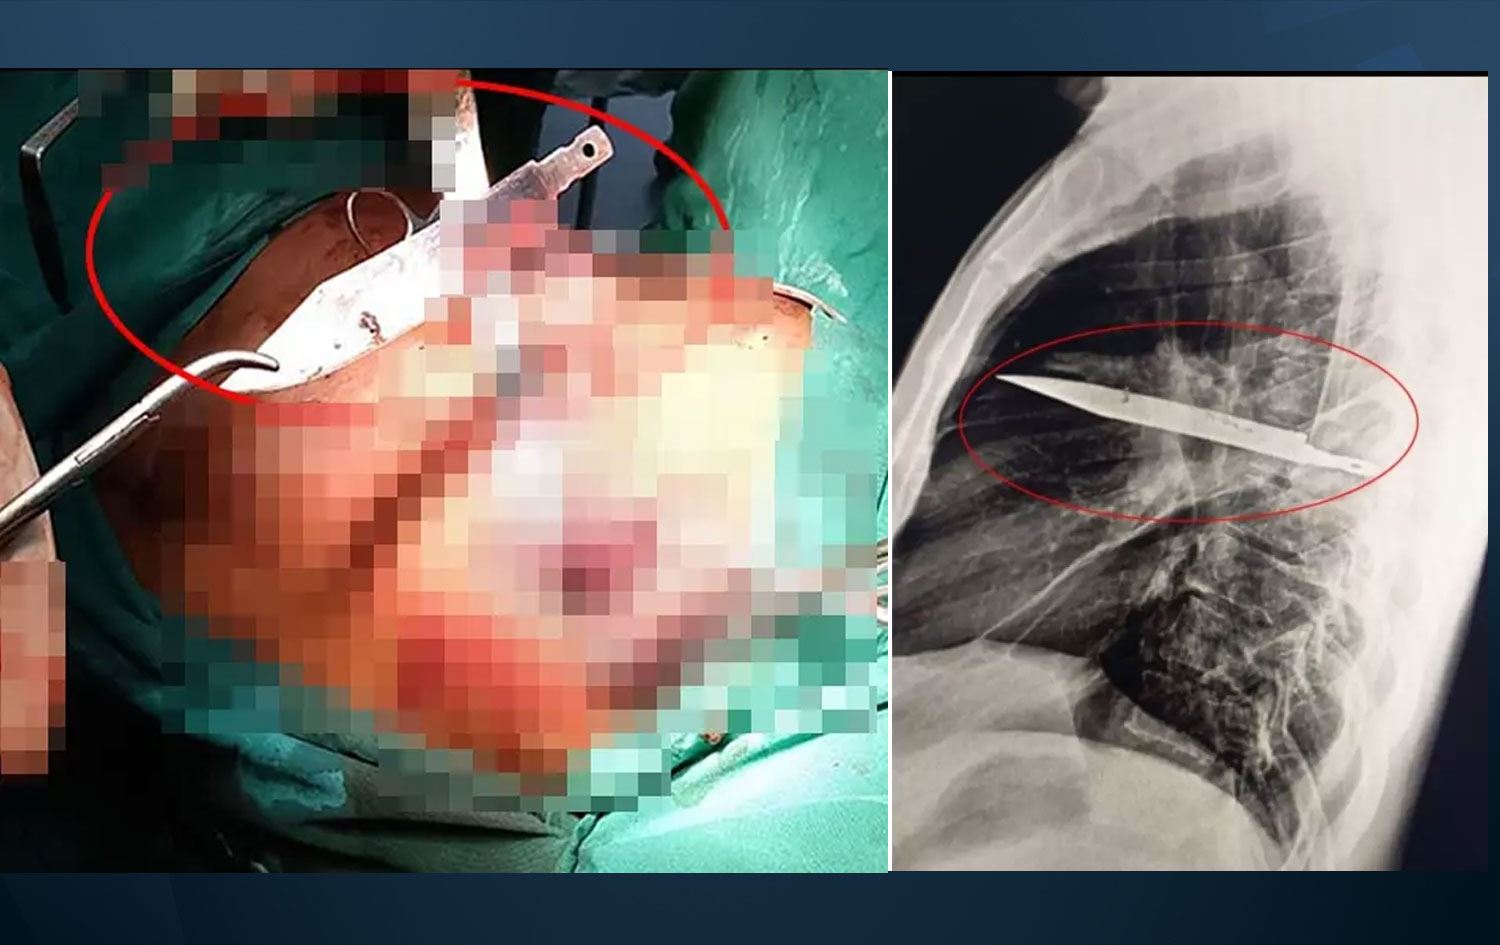

Göğüs ağrısıyla gitti, 8 yıldır göğsünde bıçakla yaşadığı ortaya çıktı